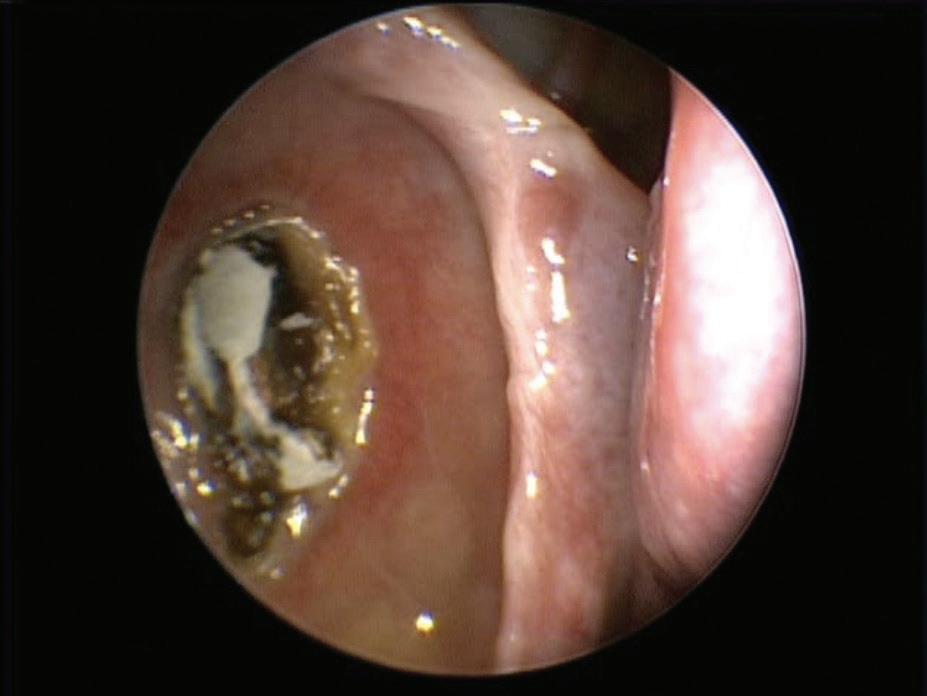

Iatrogenic external auditory canal cholesteatoma with mastoid erosion

A 70-year-old man who had undergone postauricular underlay myringoplasty to treat chronic otitis media 10 years earlier presented with a 6-month history of hearing impairment, aural fullness, and occasional otorrhea of the right ear. Otoscopy revealed a large, bulging mass on the posterosuperior aspect of the external auditory canal (EAC); the tympanic membrane was invisible (figure 1). Computed tomography of the temporal bone revealed a right-sided, 2 × 2-cm soft-tissue mass in the EAC, with erosion of mastoid air cells but a normal eardrum and middle ear cavity.

Considering the postsurgical history and the site of the mass, we diagnosed an iatrogenic EAC cholesteatoma. A whitish, spherical mass was identified on surgical exploration and was completely removed through the prior postauricular incision (figure 2). We subsequently performed canalplasty with EAC

defect reconstruction using fragments of conchal cartilage. The pathologist’s report revealed histopathologic features compatible with cholesteatoma. No evidence of recurrent disease was present during the 5-year follow-up.

Iatrogenic EAC cholesteatoma is a rare complication developing after myringoplasty. The precise incidence of the disease remains unknown. We speculate that inversion or malpositioning of a tympanomeatal flap, or unintentional implantation of epithelium during the prior surgery, causes the subsequent defect.1,2

Figure 1. Otoscopy displays a large, bulging mass in the posterosuperior aspect of the external auditory canal.

Figure 2. A spherical cholesteatoma sac is discovered during surgical exploration. Figure 2. Axial CT shows the dissected internal carotid artery (arrow) and calcified stylohyoid ligament (asterisk).